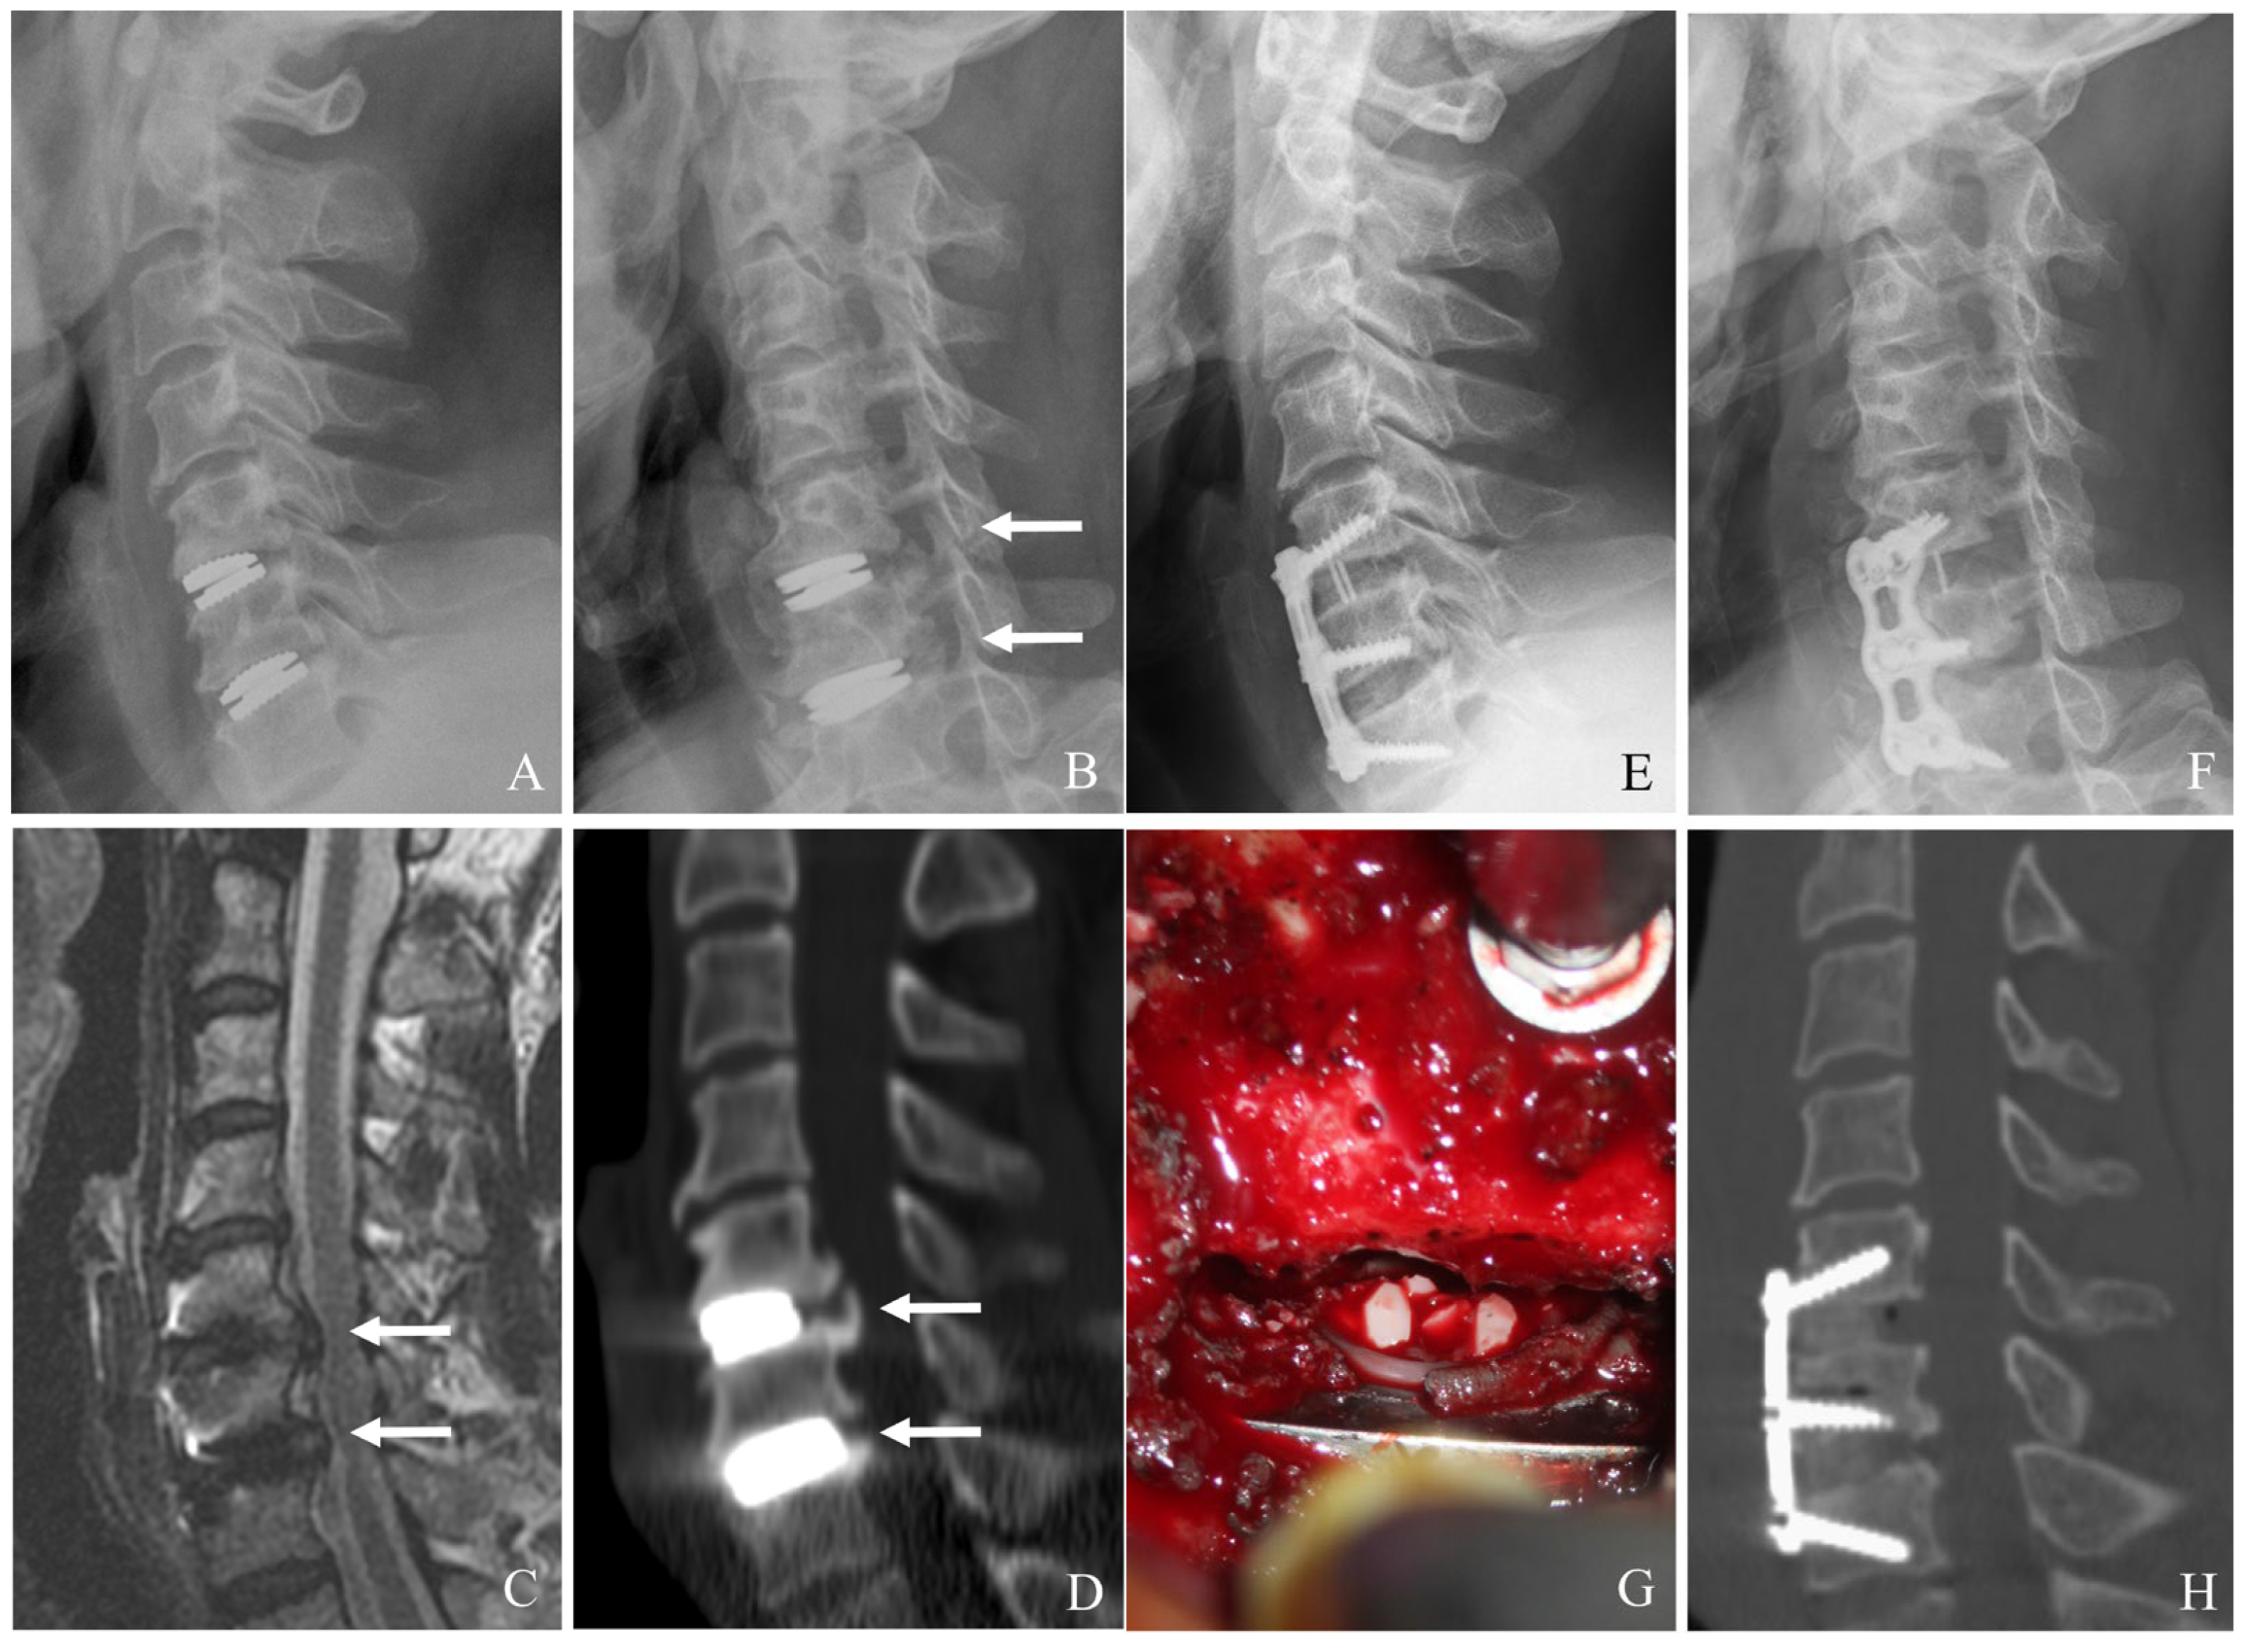

Laminoplasty is a motion-preserving posterior decompression technique particularly useful for multilevel cervical stenosis without significant instability. It expands the spinal canal while maintaining the integrity of posterior elements (Figure 6A–H) [22,23,24,25,26]. Key indications include the following:

Figure 4. Plain X-rays (A), magnetic resonance image (B), and computed tomography (C) showing subsidence and retropulsion of cervical disc arthroplasty at C5–6 with retropharyngeal (white arrows) and epidural abscess causing cord compression. The patient underwent the removal of the C5–6 prosthesis and combined C5–6 anterior cervical discectomy and fusion and posterior fusion with lateral mass screws (D).

Figure 6. Plain X-rays (A), magnetic resonance image (B,C), computed tomography (D), and clinical photo (G) showing hypertrophy of ligamentum flavum at C4–6 and facet cyst at C4–5 causing cord compression (white arrows). The patient underwent C4accept–6 open-door laminoplasty and removal of facet cyst, leading to complete cord decompression (E,F,H).